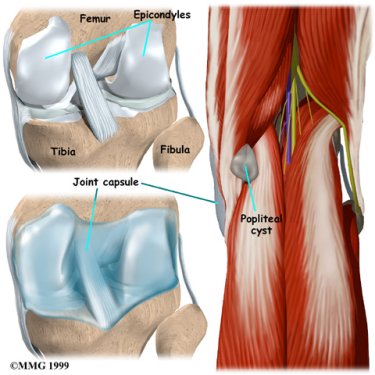

The knee joint is formed where the thighbone (femur) meets the shinbone (tibia). A slick cushion of articular cartilage covers the surface ends of both of these bones so that they slide against one another smoothly. The articular cartilage is kept slippery by joint fluid made by the joint lining (the synovial membrane). The fluid is contained in a soft tissue enclosure around the knee joint called the joint capsule.

A popliteal cyst is a small, bag-like structure that forms when the joint lining produces too much fluid in the knee. The extra fluid builds up and pushes through the back part of the joint capsule, forming a cyst. The cyst squeezes out toward the back part of the knee in the area called the popliteal fossa, the indentation felt in the back part of the knee between the two hamstring tendons and the top part of the calf muscle.

The goal of surgery is to remove the cyst and repair the hole in the joint lining where the cyst pushed through. Unfortunately, about half of the time the cyst comes back, or recurs, after being removed. Surgeons are cautious when suggesting surgery to remove a popliteal cyst because they are prone to recur. The cure is often permanent, but preventing further cysts depends a great deal on the success of treating the underlying cause. You should be aware that there is a very real chance that your cyst may return after being removed and there is no guarantee that the surgery will be successful.

The cyst is then located and separated from the surrounding tissues. The area of the joint capsule where the cyst appears to be coming from is identified.

A synthetic patch may be sewn in place to cover the hole in the joint capsule left by the removal of the cyst.